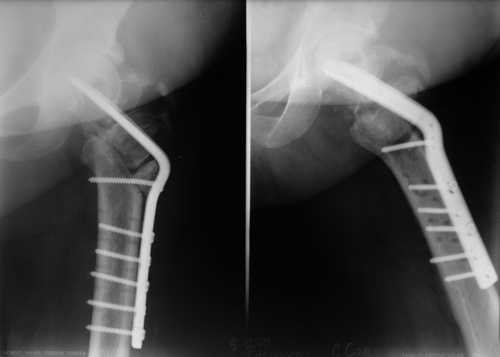

Вложение не в текстовом формате было извлечено…

Имя     : 444.jpg

Тип     : image/jpeg

Размер  : 52726 байтов

Описание: отсутствует

Url     : http://weborto.net:8080/pipermail/ortho/attachments/20081209/78733bb5/attachment-0007.jpg